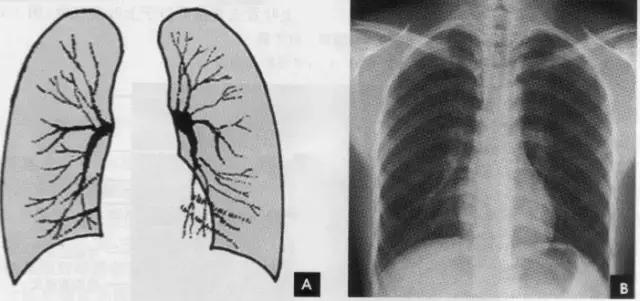

(七)肺纹理

肺纹理为自肺门向肺野呈放射状分布的树枝状阴影,它主要是肺动脉的投影,肺静脉、支气管和淋巴管也参与形成。平片可显示肺纹理的多少,粗细.分布,有无扭曲、变形与移位等。肺纹理由肺门向外围延伸,逐渐变细,至肺野外带渐细小而稀少,距侧胸壁内缘约1cm范围内的肺野基本无肺纹理可见(图下图)。